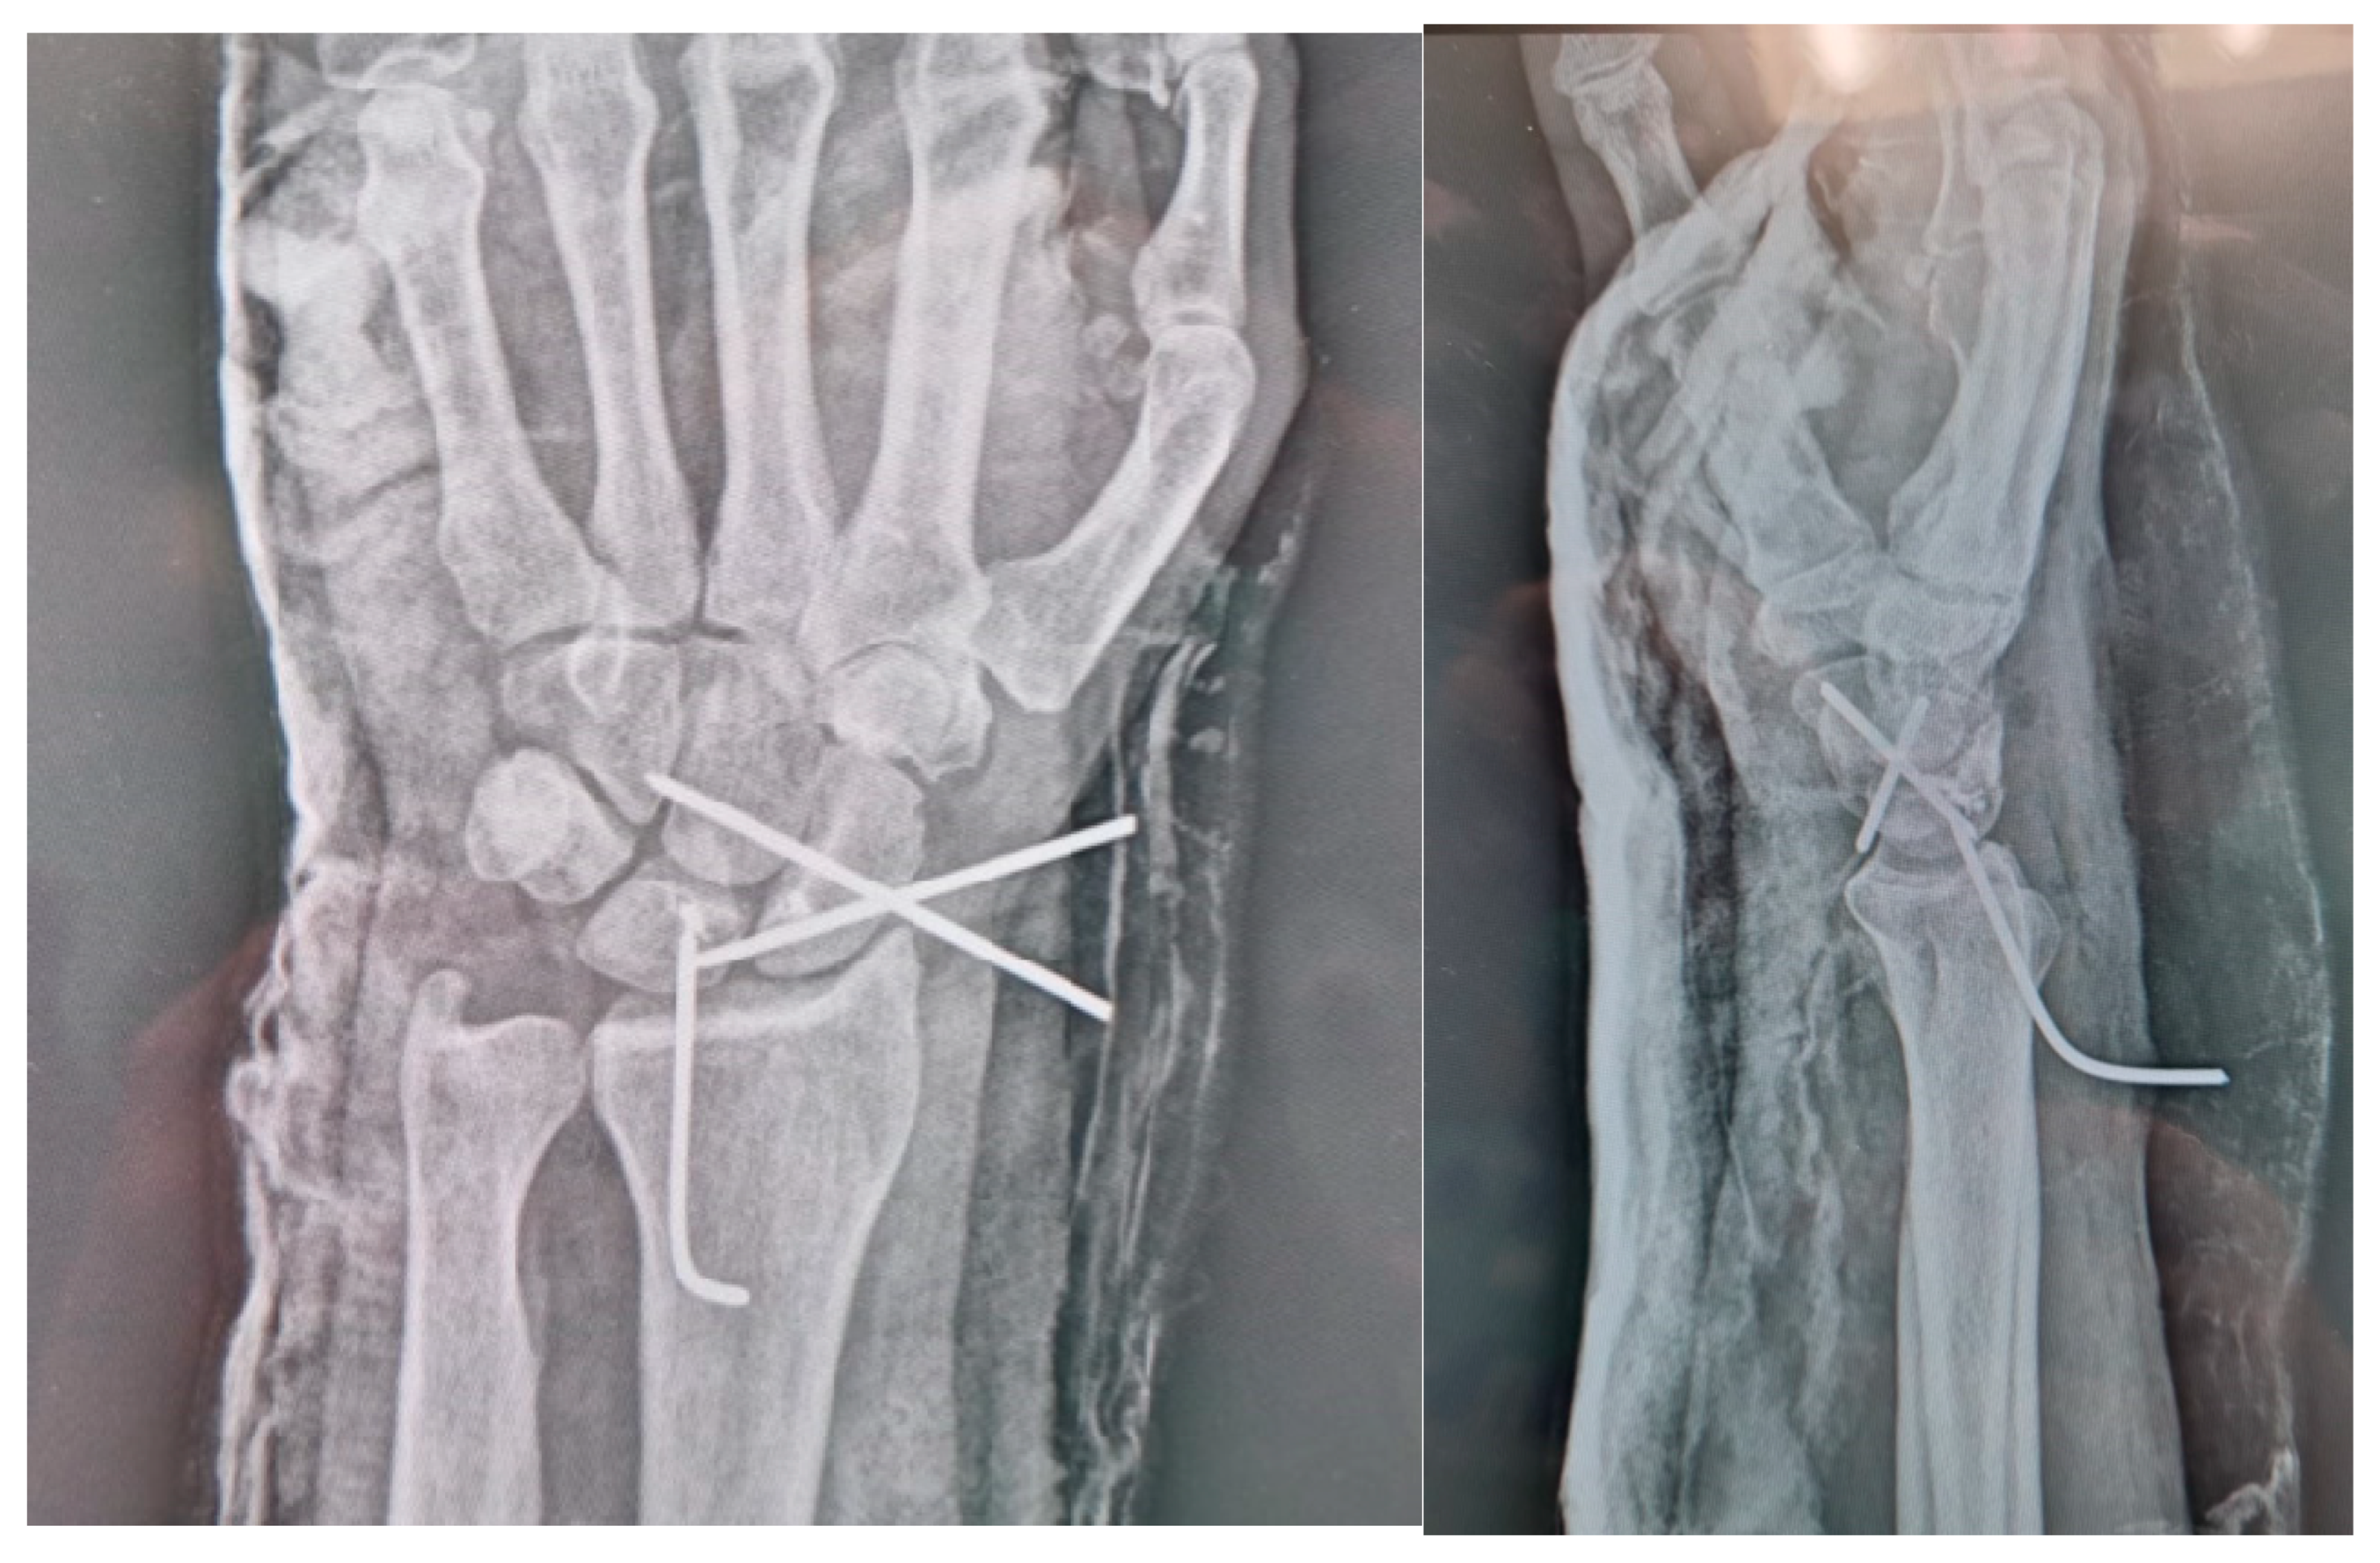

2.3. Surgical Technique

2.3.2. Surgical Procedure

2.3.3. Post-Operative Treatment and Rehabilitation